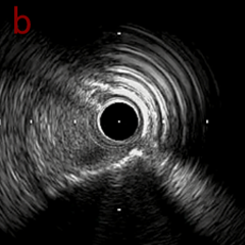

IVUS imaging after low speed 3回

OAS low speedによる引きのsandingを3回行いIVUSを確認するとa-cでは心筋側側へのOASによる良好なbias変化と、それに伴いdの健常側への危険なbias変化を認めた。

そのためcでIVUSマーキングを行い、その点より引きで赤線のpinpoint OAS high speedを行い、dに関してはinjury回避のためにOASを当てない方針とした。